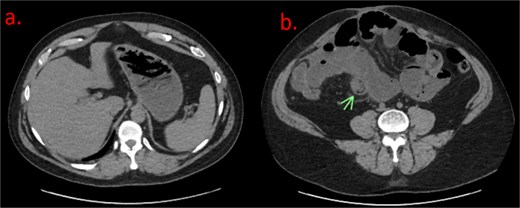

Due to the patient’s history, the surgeon ordered another CT scan with oral contrast to further examine the fluid-filled stomach (Fig. 2). Image C shows greater visualization of filling defects within the stomach consistent with foreign body ingestion. In image D, the previously suspected intussusception now appears as a foreign body measuring 3.6 cm.

(a) Axial CT of the abdomen with oral contrast shows filling defects with stacked, linear objects in the stomach, consistent with possible foreign body ingestion. (b) Axial CT with oral contrast shows dilated loops of small bowel, with a triangular intraluminal filling defect. The previously noted “bowel-within-bowel” appearance is no longer seen. Possible foreign body defect that measured ~3.5 cm in length.